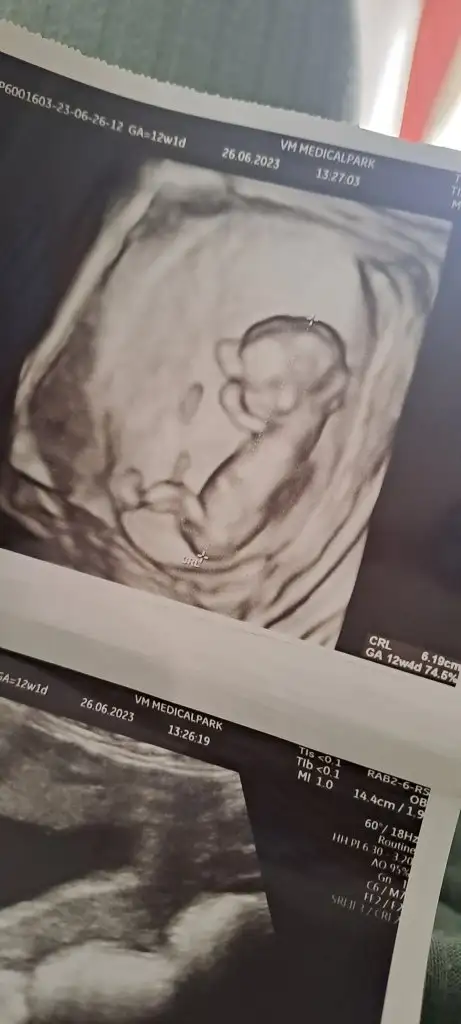

Z Zzzzz00 canım bana da tahminde bulunur musun lutfen 12+1 haftalik teşekkür ederim

• 20230626_160402.webp

13,4 KB · Görüntüleme: 43

• 20230626_155209.webp

20,3 KB · Görüntüleme: 43

• 20230626_155202.webp

17,9 KB · Görüntüleme: 44